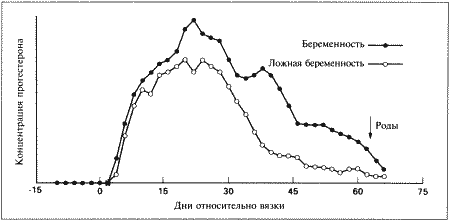

Фиг. 2.1.

Изменения концентрации прогестерона в плазме крови при физиологической и ложной беременности. Воспроизведено из кн. Lane и Cooper «Veterinary Nursing», (1994) с разрешения Butterworth Heinemann

У кошек как при беременности, так и в ее отсутствие — концентрация прогестерона в плазме начинает повышаться после овуляции, через 24–50 часов после выброса ЛГ. Максимальные показатели прогестерона (100–200 нмоль/л) наблюдаются на 20–25 день после первой вязки.

При ложной беременности концентрация прогестерона начинает снижаться приблизительно на 25 день и достигает базального уровня на 30–40 день. Такое постепенное снижение концентрации прогестерона является характерной особенностью ложной беременности у кошек. При истинной (физиологической) беременности концентрация прогестерона поддерживается на высоком уровне в течение всего периода вынашивания и стремительно снижается перед родами. Постепенное снижение концентрации прогестерона в конце ложной беременности у кошек сходно с тем, что наблюдается у собак, и, вероятно, объясняется отсутствием лютеолитического фактора, вырабатываемого в организме самок в конце беременности. Очевидно, на 25–35 день ложной беременности желтые тела, лишенные лютеотрофической поддержки со стороны эмбрионов и плаценты, подвергаются «запрограммированной» атрофии. Гистероэктомия, выполненная во время лютеиновой фазы ложной беременности, не отражается на жизнеспособности желтых тел, что свидетельствует о том, что матка не участвует в процессе рассасывания желтых тел.